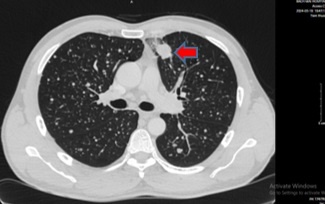

Tại đây, kết quả chụp cắt lớp vi tính lồng ngực của ông C. phát hiện một khối đặc tròn, bờ tua gai, kích thước 28x24 mm ở thùy trên phổi trái, có hình ảnh ngấm thuốc không đồng nhất. Ngoài ra, bác sĩ còn phát hiện nhiều hạch cạnh khí quản, rốn phổi và hố thượng đòn hai bên.

Phổi trái nhu mô ngoại vi thùy trên có khối đặc tròn bờ tua gai, kích thước 28x24 mm (mũi tên màu đỏ), ngấm thuốc không đồng nhất sau tiêm. Ảnh: BVCC.